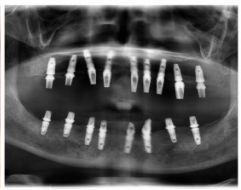

種牙后X光片,未戴冠。

種牙后X光片,戴冠。

通過(guò)X光片可以看到,醫(yī)生雖然盡量設(shè)計(jì)連冠種植,但還是用了十七個(gè)植體,盡管已經(jīng)是多次調(diào)整后的精簡(jiǎn)方案,但手術(shù)時(shí)長(zhǎng)依然長(zhǎng)達(dá)一天。位老先生之前在另一家醫(yī)院咨詢時(shí),醫(yī)生給的方案是種二十二個(gè)植體,光是種植費(fèi)用就令人大呼“害怕”了。